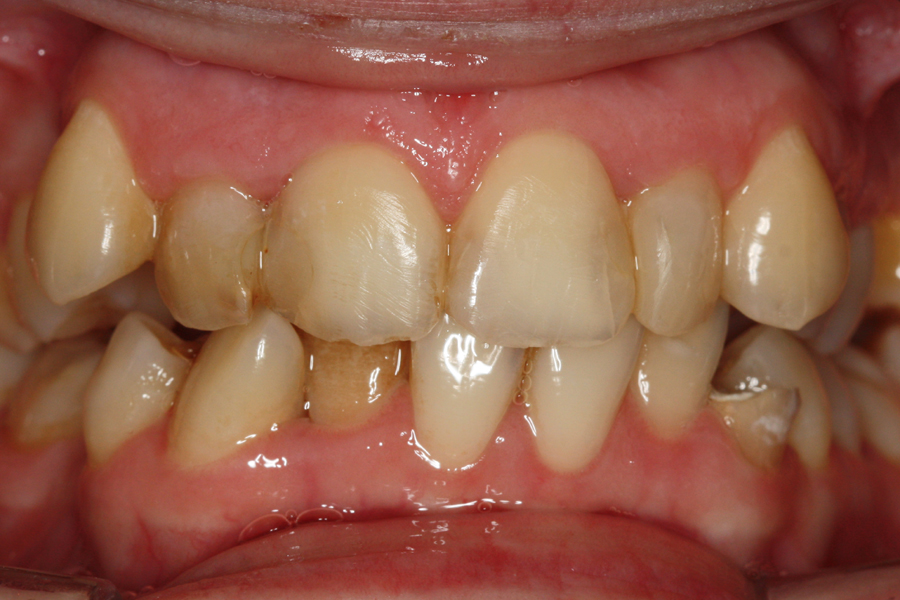

Młoda pacjentka zgłosiła się do naszego gabinetu celem wykonania kompleksowego leczenia zachowawczo-ortodontycznego. Oprócz problemów natury ortodontycznej stwierdzono złą higienę jamy ustnej oraz liczne potrzeby leczenia zachowawczo-endodontycznego. Po wnikliwej analizie telerentgenowskiej oraz analizie modeli zadecydowano o ekstrakcji 2 zębów w łuku dolnym (kła po stronie lewej oraz pierwszego przedtrzonowca po stronie prawej). Plan leczenia obejmował ponadto zamknięcie łuku po brakujących zębach w łuku górnym. Leczenie aktywne trwało 2 lata i 8 miesięcy. W czasie jego trwania pacjentka była regularnie poddawana zabiegom higieny profesjonalnej celem eliminacji zapaleń przyzębia brzeżnego. Po leczeniu aktywnym zastosowano leczenie retencyjne w postaci retainera stałego w żuchwie oraz szyny retencyjnej w łuku górnym.